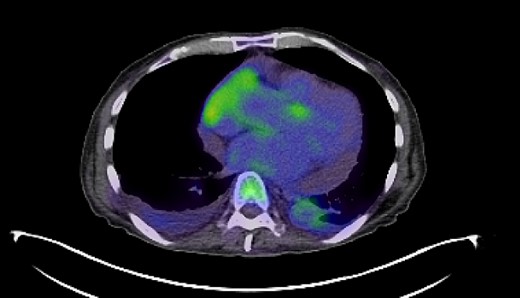

In response to the initial intraocular lymphoma diagnosis, the patient received intraocular rituximab treatment with a promising initial response. However, the subsequent emergence of fevers, chills, night sweats and muscle weakness with evidence of pleural and pericardial effusions necessitated additional interventions, including pericardiocentesis and thoracentesis, revealing the systemic progression of the lymphoma. Pericardiocentesis and thoracentesis both showed aggressive lymphoma that was CD20-, CD38- and CD45-positive and CD5-, CD10- and CD11C-negative. KI67 was increased in 50% of cells. PET-CT showed FDG-AVID right-sided pleural effusion and moderate-large pericardial effusion with foci of mild FDG uptake anteriorly (Fig. 2). He was treated with three cycles of R-EPOCH that was stopped after the patient experienced severe fatigue and weakness. PET again showed no evidence of disease.

PET-CT imaging indicating pericardial and pleural involvement of lymphoma.

Treatment strategies for PVRL range from systemic high-dose methotrexate, chemotherapy adjunct with stem-cell transplant, and single-agent treatments like ibrutinib, lenalidomide and temozolomide [4]. In this case, intraocular rituximab was initially employed to target CD20-positive B cells within the eye. However, the systemic progression of DLBCL, as evidenced by pleural and pericardial effusions and later CNS involvement, necessitated high-dose methotrexate and rituximab to address CNS disease burden, underscoring the aggressive nature of the disease and the challenges in achieving disease control (Figs 2 and 3).